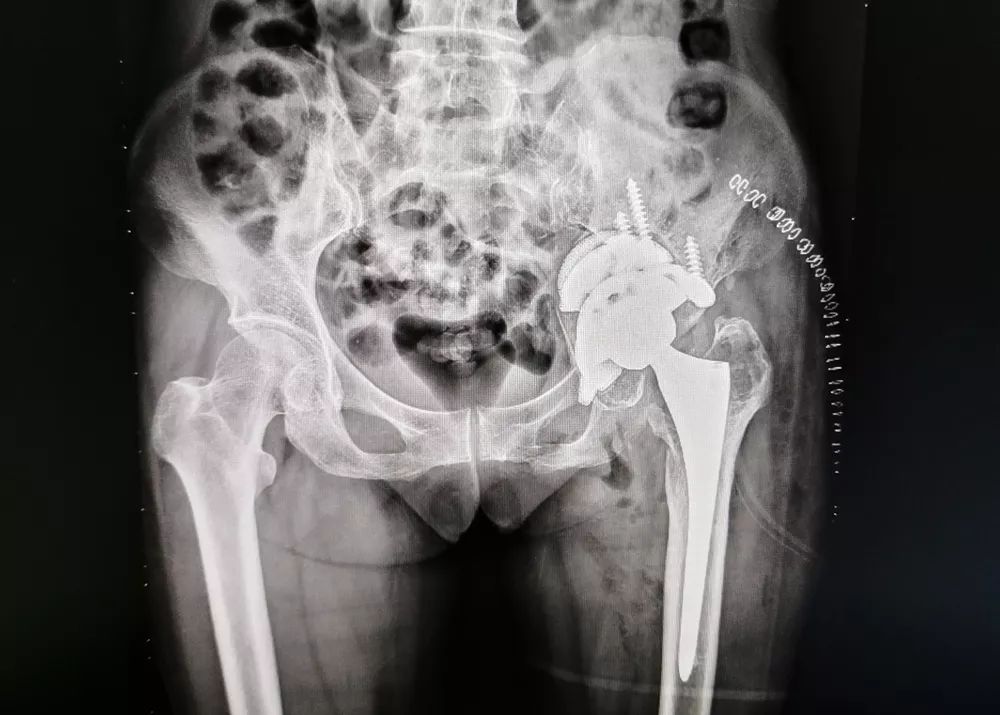

手术后

↓3D打印髋臼模型

↑3D打印假体

骨三科医护团队马上紧锣密鼓地投入到术前准备工作中。经评估,患者无绝对手术禁忌症,叶主任决定先通过CT扫描获得髋臼缺损的三维数据及原有假体的三维数据,采用目前先进3D打印技术,重建患者左侧髋臼模型及原有假体模型,同时结合3D打印模型量身定制重建髋臼的内固定物及适合取出原有假体的工具,并采用患者第一次术口入路,减少患者创伤,历经3小时,顺利完成手术。术中、术后影像学资料显示,患者重建髋臼的形态良好,假体及内固定物固定牢固。在茂名市中医院骨三科医护人员的精心照顾下,仅仅一个星期,患者就能重新站起来并行走,身体也一天天好起来。